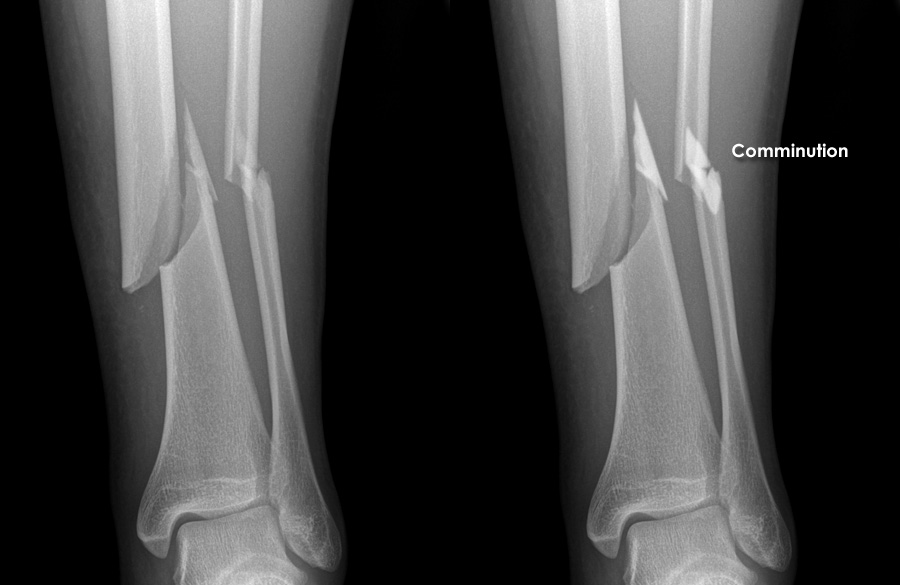

• Fractures: Commonly affecting the hip, femur, tibia, fibula, and ankle bones.

• Imaging: X-rays, MRI, and CT scans provide detailed views of bone and soft tissue damage for precise diagnosis.

• Fracture Fixation: Severe fractures may require plates, screws, or rods to realign and stabilise bones.